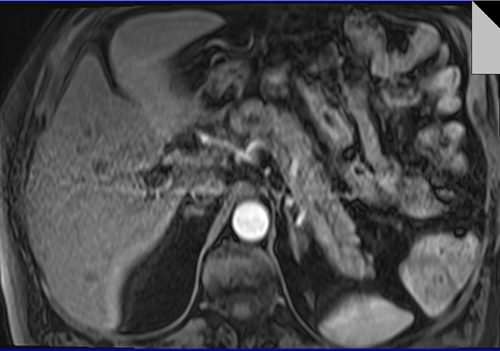

PANCREAS MRI DYNAMIC T1 ARTERIAL PHASE IMAGES